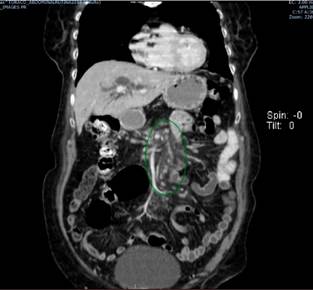

This is the case of a 72-year-old female patient with a biliary obstruction secondary to a mass located in the head of the pancreas. The following findings were reported in her paraclinical tests: laboratory tests: initial total bilirubin levels of 12.32 mg/dL at the expense of direct bilirubin levels (10.8 mg/dL); abdominal CT scan: presence of a neoplasm in the head of the pancreas surrounding in 180° the superior mesenteric vein; patent splenoportal confluence; patent hepatic artery; dilatation of the intrahepatic and extrahepatic biliary ducts, and of the main pancreatic duct; increased density of mesenteric fat with lymph nodes with short axes (between 5 mm and 6 mm) suspicious due to their enhancement; and focal hepatic lesion in the segment 6 with an appearance suggestive of suspected neoplastic infiltration, without presence of free fluid (Figures 1 and 2).